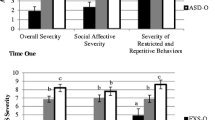

Comparison of FXS subgroups: with and without autism

We identified children in the FXS group who also met criteria for autistic disorder, referred to as FXS with autism (“FXS+Aut”). The children with FXS who did not meet our autism criteria were labeled as FXS without autism (“FXS−Aut”). Membership in the FXS+Aut subgroup required meeting cut-offs for autistic disorder on the ADI-R and the ADOS-G. Using this classification scheme, there were 17 children with FXS (33%) who also met criteria for autistic disorder. This is comparable to the rate of autistic disorder observed in toddlers and preschoolers with FXS reported by Rogers et al. 2001. Age adjusted means for the FXS subgroups were similar to those observed in the total FXS sample. Percent differences in substructure brain volumes for FXS, AUT, and FXS+Aut groups compared to the controls are displayed in Fig. 1. Comparison of the FXS+Aut group to the AUT group revealed significant CN enlargement (p < .001), and significantly smaller AMY (p < .001). The CN enlargement in the FXS+Aut and FXS−Aut groups compared to controls was dramatic in comparison to the AUT group. However, these groups showed opposite trends in their AMY volume, with the AUT group showing enlargement but the FXS groups showing decreased volume compared to controls. There were no significant differences in CN volume between the FXS+Aut and FXS−Aut groups, but both of these groups had significantly larger CN volume compared to the AUT group (see Fig. 2). Volumes of the AMY for the FXS+Aut and FXS−Aut were significantly smaller than in the AUT group, and there was approximately a 5% difference (not significant) between the FXS+Aut and FXS−Aut subgroups (see Fig. 2). As was observed in the overall FXS group comparison, we observed a double dissociation of greatly enlarged CN and small AMY in FXS, regardless of autism status.

Exploratory analyses were conducted to determine whether brain–behavior relationships differed between the FXS+Aut, FXS−Aut, and AUT groups. ADI-R subdomain scores are presented in Table 4. Examination for clinical correlates using global autism measures (ADI-R algorithm subdomain scores; ADOS algorithm domain scores) as well as more refined measures of repetitive behaviors (e.g. RBS-R) did not reveal any significant brain-behavior correlations in any of these groups (FXS+Aut, FXS−Aut, AUT).

In this study we observed significant differences in the neuroanatomical profiles of male children with autistic disorder with FXS relative to those who did not have FXS. Specifically, boys with both FXS and autism had substantially enlarged CN volume and smaller AMY volume compared to boys with FXS without autism. In contrast, boys with idiopathic autism (no FXS) had only modest enlargement in their CN volumes compared to controls, but more robust enlargement of their AMY volumes. Although observing this double dissociation among selected brain volumes, no significant differences in severity of autistic behavior as measured by subdomains of the ADI-R were detected between these two study groups. This study therefore provides evidence of a substantially different pattern of brain structures in two clinical populations with presentations of autistic behavior. The findings in the present study suggest that heterogeneity may be underestimated in studies attempting to identify common biological underpinnings of individuals meeting DSM IV behavioral criteria for the behaviorally defined syndrome of autism (e.g., genetic linkage studies). Clearly the study of biological mechanisms underlying autistic behavior in etiologically-defined subgroups such as those with FXS, is an important and probably under-employed strategy for dealing with the heterogeneity issue.

The finding of enlarged CN in FXS is consistent with other studies finding enlargement of the CN in FXS [12, 28, 48], and the magnitude of enlargement (∼40%) suggests this is a robust finding in children with FXS. The CN has been implicated in the repetitive behaviors seen in both autism and FXS. One possible cause for such an enlargement of the CN in FXS may be linked to the underlying genetics of the disorder. An association has been reported between a measure of FMR1 gene inactivation (activation ratio-AR) with caudate volume, and an association of IQ with both caudate and ventricular volumes [49]. We also know that FMRP has also been shown to play a direct role in brain development [50] and decreased FMRI protein has been associated with the cognitive deficits seen in FXS [51–54]. The significant CN enlargement observed in FXS, in this study almost 3–4 times greater than in controls and about 3 times greater than cases with autism, may be more related to the FXS mutation versus diagnosis of autism, since the findings in the FXS autistic and non-autistic individuals are the same as those in the overall FXS group, regardless of autism status.

We report decreased AMY volume in our FXS group (with and without autism) and enlarged AMY in our AUT group. Our finding of increased AMY volume in our AUT sample is consistent with other reports of increased AMY in young children with autism, where AMY enlargement has also been associated with deficits in social behavior [21, 55] and social orienting [26]. Our finding of decreased AMY volume in boys with FXS is contrary to some reports of AMY enlargement in FXS [28], but consistent with studies that included very young children [48]. Dalton and colleagues hypothesized that early AMY enlargement is the result of amygdalar hyperactivity and hypertrophy, in response to the aversive nature of social stimulation in autism, with subsequent decreased AMY volume occurring as the aversive stimulation becomes chronic [56, 57]. Here we find support to suggest that children with FXS have decreased AMY despite having social deficits characteristic of autism. On the other hand, children with autism have enlargement of the AMY, yet display the same behaviors. It may be that having an AMY either too large or too small are ‘two sides of the same coin’ in the same way that hyper or hypo function of the MECP2 gene both result in the Rett Syndrome phenotype [58].

We did not find phenotypic differences in autistic behavior, as measured by the ADI-R and ADOS in our FXS+Aut and AUT groups. The defining features of autism as they appear in the DSM, while perhaps good ways to characterize the most impairing clinical features of autism, are not necessarily the best phenotypic features for separating out the underyling etiologic heterogeneity. Other behavioral features such as hyperarousal, thought to be more characteristic of FXS, may better distinguish groups of autistic individuals with and without FXS and may eventually find a place in studies of the autistic phenotype. Clearly additional studies which seek to identify different behavioral profiles in autistic individuals with and without FXS would provide important clues to meaningfully subsetting the autism phenotype.